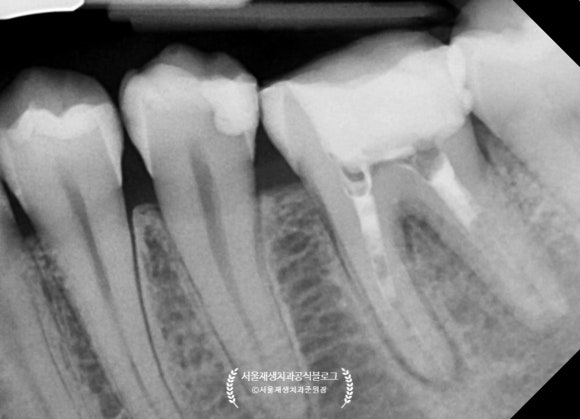

치근단 엑스레이를 살펴보겠습니다.

신경치료 후에 크라운으로 치아를 보호해주지 않고,

빈 구멍만 메워둔 상태로 몇년이 지났다고 합니다.

구멍을 메꾸는 재료만으로는

어금니의 씹는 힘을 충분히 견디기가 힘듭니다.

시간이 지남에 따라 재료가 마모되고 깨지면서

입 안의 세균들이 다시 치아 내부로 침투하게 되지요.

때워놓은 재료가 오래되어

하방으로 충치가 생기고 있었습니다.

신경치료 받은 치아에 충치가 다시 생긴다는 것은,

어금니 신경치료에 들인 공이 와르르 무너지는 것과 같습니다.